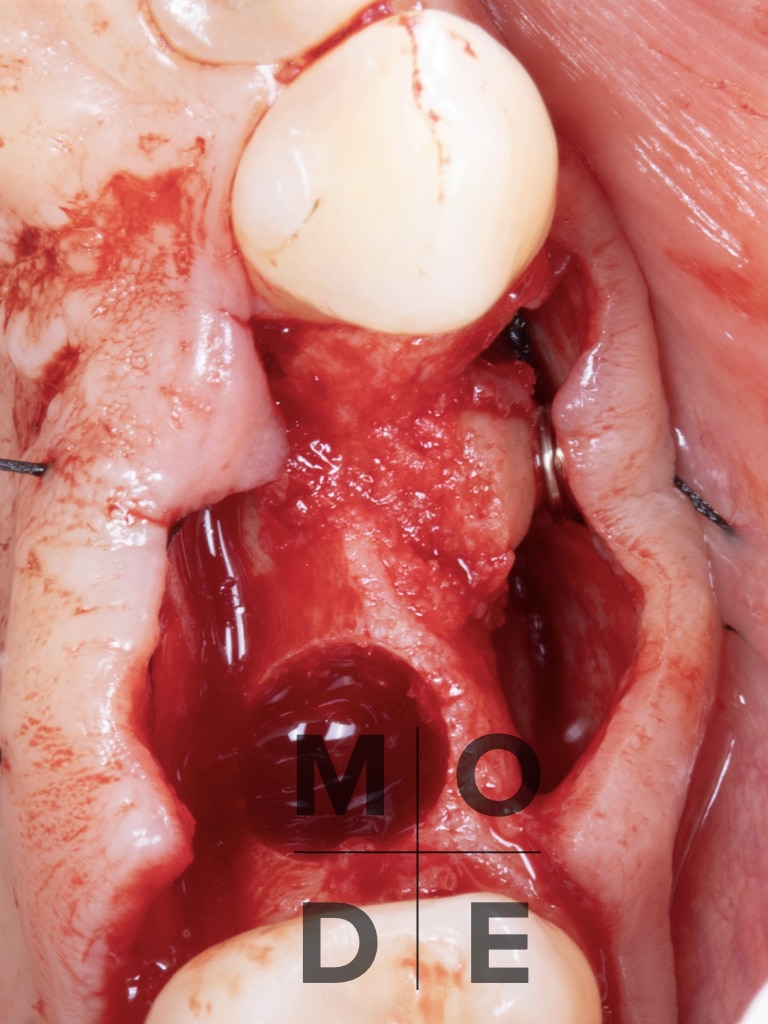

Vertical and Horizontal Defect at tooth 14

Cortical Lamina of Bone Block harvested from the palatal side of tooth 15

Particulated Bone Graft